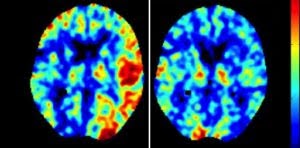

Brain Perfusion Heatmap

Brain perfusion heatmap demonstrating successful changes (reduction in areas of low blood flow) after revascularization surgery.